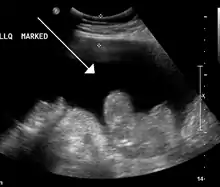

Ultrasound investigation is often performed prior to attempts to remove fluid from the abdomen. This may reveal the size and shape of the abdominal organs, and Doppler studies may show the direction of flow in the portal vein, as well as detecting Budd-Chiari syndrome (thrombosis of the hepatic vein) and portal vein thrombosis. Additionally, the sonographer can make an estimation of the amount of ascitic fluid, and difficult-to-drain ascites may be drained under ultrasound guidance. An abdominal CT scan is a more accurate alternate to reveal abdominal organ structure and morphology.[11]

- Grade 1: mild, only visible on ultrasound and CT